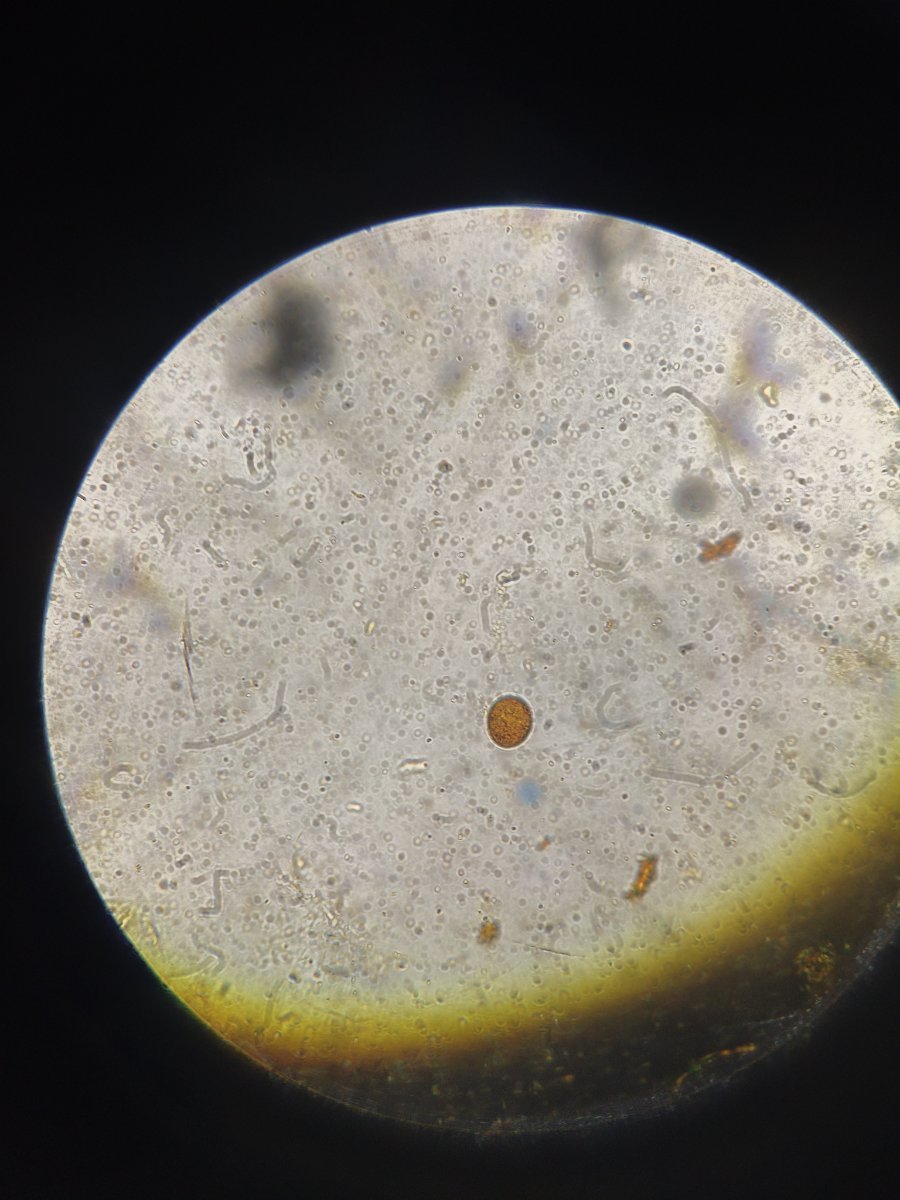

Здравствуйте. Помогите, пожалуйста, разобраться. Волнистый попугай, девочка, 3 года 5 месяцев. Лечили мегабактериоз, на вчерашней микроскопии ни одной мегабактерии, однако рвота и непереваренные зерна в помете остаются. Сделали рентген, орнитологи в замешательстве, у каждого свое отличное мнение по поводу преджелудка , печени и новообразовании в лёгких. В помете также нашли много пыльцы, однако возможно , что это глисты. Снова не понятно. Помогите , пожалуйста, разобраться с рентгеном и микроскопией. Фото прикладываю.